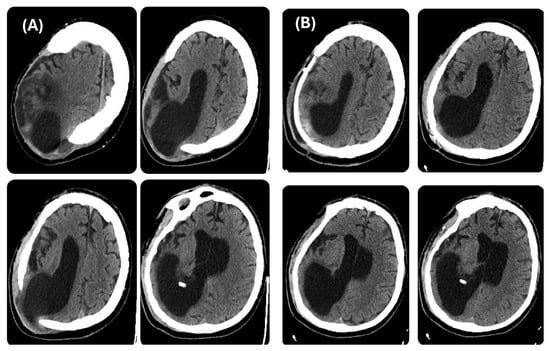

During his LTC stay, the patient was monitored with repeated CT scans. The last brain CT scan carried out before reconstructive CP (Figure 2A) showed further right occipital horn enlargement with persistence of protrusion of the brain parenchyma at the craniectomy site. One month after the CP, a CT scan was repeated, revealing patches of blood-like hyperdensity in the cortico-subcortical location corresponding to the posterior horn of the right lateral ventricle at the surgical site, with persistent significant right ventricle dilatation (Figure 2B).

Figure 2. Brain CT scan, axial view. Left side (A) before cranioplasty and right side (B) after cranioplasty.